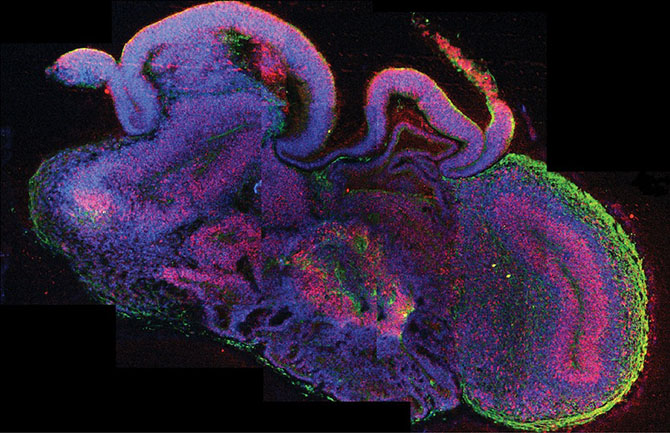

Исследователи из Австрии сделали большой шаг в области исследований мозга — они в буквальном смысле вырастив мозг. Радует то, что этот мозг не плавает в банке, скорее это «мозговые органоиды» всего четырёх мм в диаметре, выращенные из стволовых клеток человека в чашке Петри. Этот так называемый мини-мозг представляет собой первый случай, когда учёные смогли создать что-то близкое к мозговой ткани в лабораторных условиях. Безусловно, до разумной сущности ещё далеко, но благодаря мини-мозгу удалось узнать, как развивается редкое заболевание под названием микроцефалия. Кроме того, подобные образцы можно использовать для диагностики и лечения других заболеваний вроде аутизма и шизофрении.